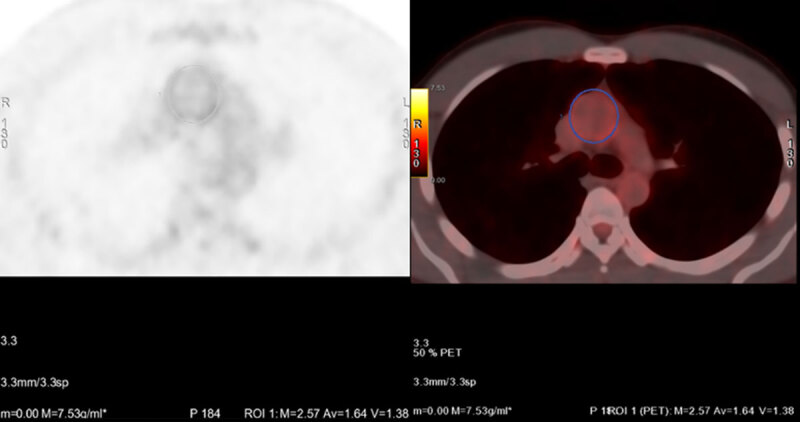

Objective: The objective of this study was to evaluate the inter-observer variability of both qualitative visual grading of aortic 18F-FDG uptake and the quantitative aortic mean and maximum SUVs in these patients with mild to moderate covid-19 infection who underwent multimodality cardiac imaging within the COSMIC-19 trial.

Study design: This is a sub-study of the COSMIC-19 trial. 30 patients were subjected to a combined Computed Tomography Coronary Angiogram and 18F-FDG PET/CT, followed by cardiac magnetic resonance. Two independent observers measured the Standardized uptake values in five regions of interest at each aortic segment. These were performed sequentially along the length of the aorta every 5 mm on the axial slices. The maximum and mean standard uptake values were measured.

Results: Qualitative assessment showed excellent agreement between observer x and y for the ascending aorta and aortic arch regions with the kappa coefficients for the inter observer agreement of 0.92 (95% CI:0.78-1.0) and 0.91 (95% CI:0.74-1.0) respectively. Quantitative assessment showed a very high positive correlation between the two observers for each of the regions measured for SUVmean as follows; ascending aorta r = 0.96 (p < 0.001), Aortic arch r = 0.90 (p < 0.001) and descending Aorta r = 0.91 (p < 0.001). The correlation coefficients for the SUVmax were substantially strong.

Conclusion: This study shows an excellent inter-observer reproducibility for both qualitative and quantitative SUVmean vascular 18F-FDG measurements in patients with COVID-19 large vessel vasculitis. Quantitative SUVmax demonstrated substantially strong interobserver reproducibility.